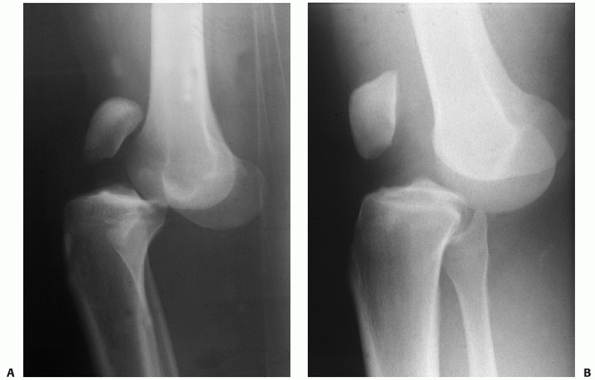

![]() |

|

FIGURE 54-10 Lateral radiographs comparing a posterior cruciate ligament (PCL)-intact knee dislocation (A) and a complete bicruciate ligament knee dislocation (B)

in two different patients. Note the parallel alignment of the patella with the femur in the complete bicruciate injury Please check placement of “A” and “B.” and (B) the close proximity of the femur and tibia in the PCL-intact knee dislocation (A). |

example, patients can sustain an anterior dislocation and have either a

bicruciate ligament injury or a PCL intact dislocation (Fig. 54-10). The position classification system does not help differentiate between these two patterns.